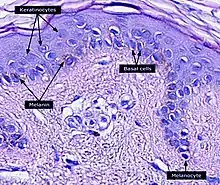

Keratinocytes are the primary type of cell found in the epidermis, the outermost layer of the skin. In humans, they constitute 90% of epidermal skin cells.[1] Basal cells in the basal layer (stratum basale) of the skin are sometimes referred to as basal keratinocytes.[2] Keratinocytes form a barrier against environmental damage by heat, UV radiation, water loss, pathogenic bacteria, fungi, parasites, and viruses. A number of structural proteins, enzymes, lipids, and antimicrobial peptides contribute to maintain the important barrier function of the skin. Keratinocytes differentiate from epidermal stem cells in the lower part of the epidermis and migrate towards the surface, finally becoming corneocytes and eventually be shed off,[3][4][5][6] which happens every 40 to 56 days in humans.[7]

Within the epidermis keratinocytes are associated with other cell types such as melanocytes and Langerhans cells. Keratinocytes form tight junctions with the nerves of the skin and hold the Langerhans cells and intra-dermal lymphocytes in position within the epidermis. Keratinocytes also modulate the immune system: apart from the above-mentioned antimicrobial peptides and chemokines they are also potent producers of anti-inflammatory mediators such as IL-10 and TGF-β. When activated, they can stimulate cutaneous inflammation and Langerhans cell activation via TNFα and IL-1β secretion.

Keratinocytes contribute to protecting the body from ultraviolet radiation (UVR) by taking up melanosomes, vesicles containing the endogenous photoprotectant melanin, from epidermal melanocytes. Each melanocyte in the epidermis has several dendrites that stretch out to connect it with many keratinocytes. The melanin is then stored within keratinocytes and melanocytes in the perinuclear area as supranuclear “caps”, where it protects the DNA from UVR-induced damage.[28]